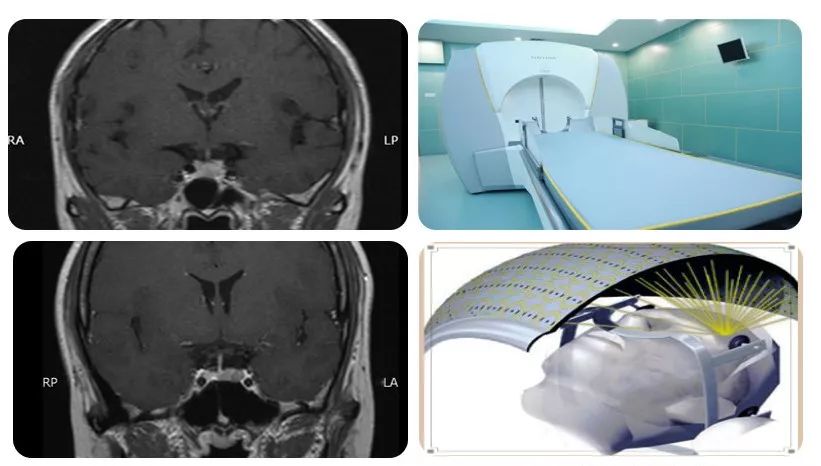

γ射线清除脑部癌细胞

图片尺寸750x463